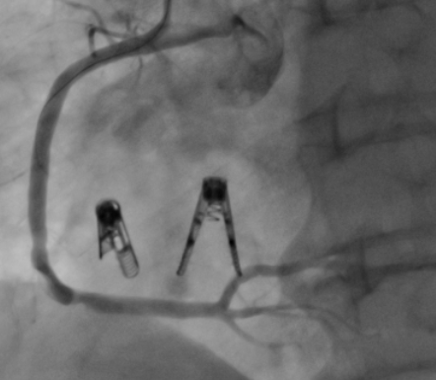

术者为患者植入2枚K-Clip,将扩大的三尖瓣环进行缩小,整个手术时间不到1小时,其中器械操作时间30分钟,即完成了手术。

术后DSA